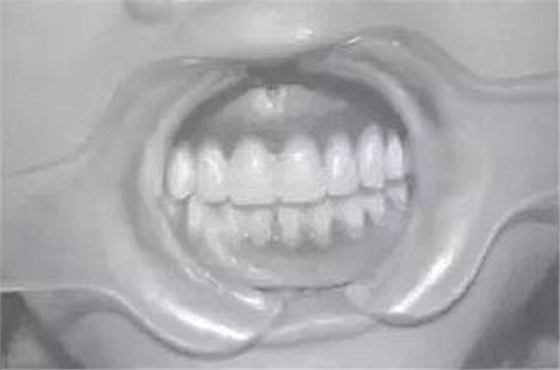

預(yù)約定時復(fù)診。完成修復(fù)后,囑患者注意合理飲食及口腔衛(wèi)生,每年復(fù)診。隨訪4年,患者自覺良好,飲食咀嚼正常,復(fù)查:臨床檢查見,16、17、26、36、46、75、85合面見充填體,26遠中面缺損平齦緣,17臨床牙冠已完全暴露于口內(nèi),27可見1/3牙冠:義齒就位后其固位及穩(wěn)定性較好、無壓痛、患者發(fā)音正常、進食正常:X線片示:75、85牙根可見根尖1/3處發(fā)生吸收、17、27牙根未發(fā)育完全;牙槽骨未發(fā)現(xiàn)吸收情況;同4年前相較而言,戴用義齒后,牙槽骨可見輕微增長。

圖3修復(fù)后口內(nèi)像